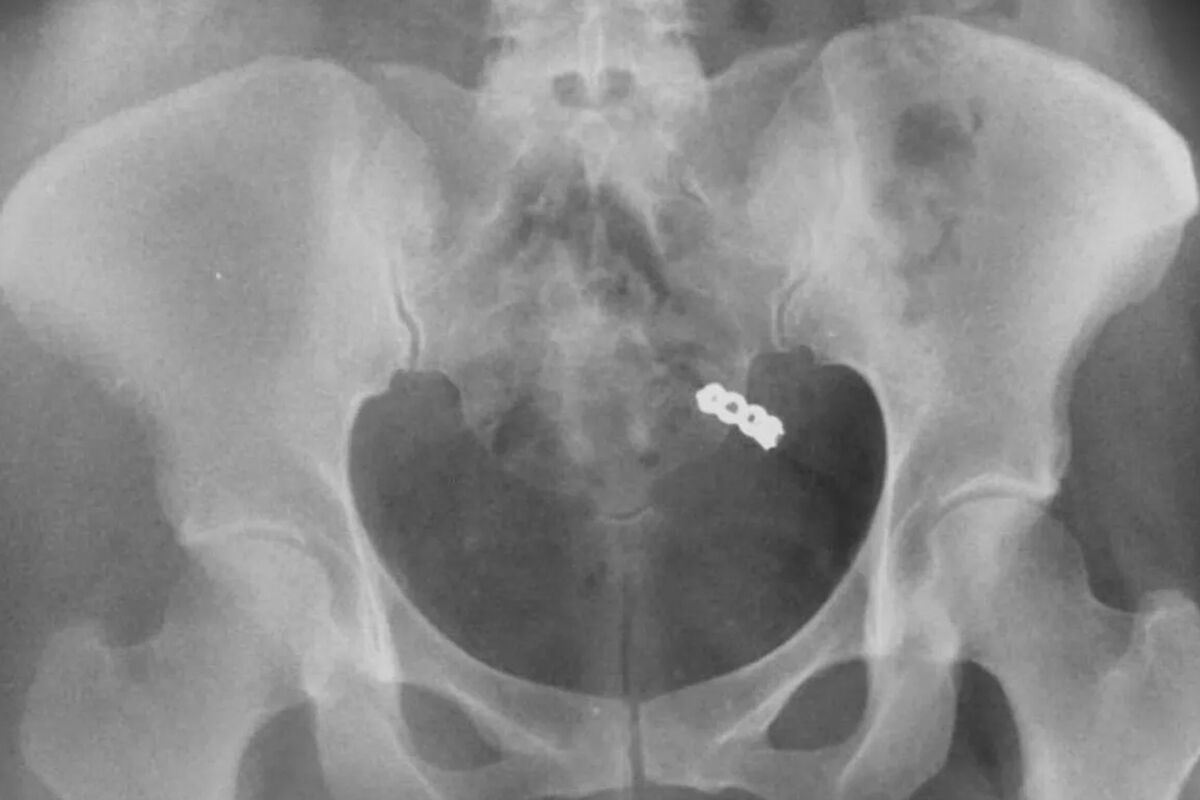

После тщательных поисков в гостиничном номере, Данна решила сделать рентген. Снимок показал, что кольцо действительно было внутри женщины. Врачи заверили ее, что переживать не нужно — украшение выйдет их организма естественным образом, что и произошло на следующий день.